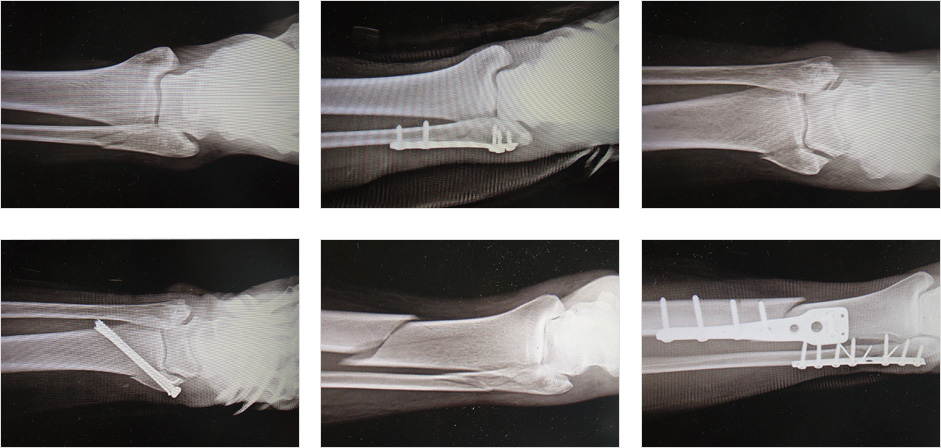

- 그 외 추락에 의한 종골(뒤꿈치뼈) 골절도 많습니다.

과거에는 그냥 방치한 경우가 많았으나 현재는 부서진 관절면을 맞추고 뒤꿈치 부위를 원래의 모양대로 교정하는 수술을 합니다.

또는 과거 종골 골절의 후유증으로 뒤꿈치의 모양이 틀어진 경우도 교정을 합니다.